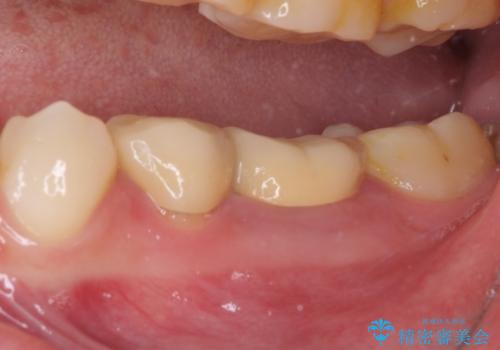

- クラウンを装着したばかりの歯の歯肉が腫れていることを気にして来院された患者様です。

むし歯がとても大きく、歯茎に歯の一部が埋もれてしまっているため、汚れが溜まりやすくなっている状態でした。